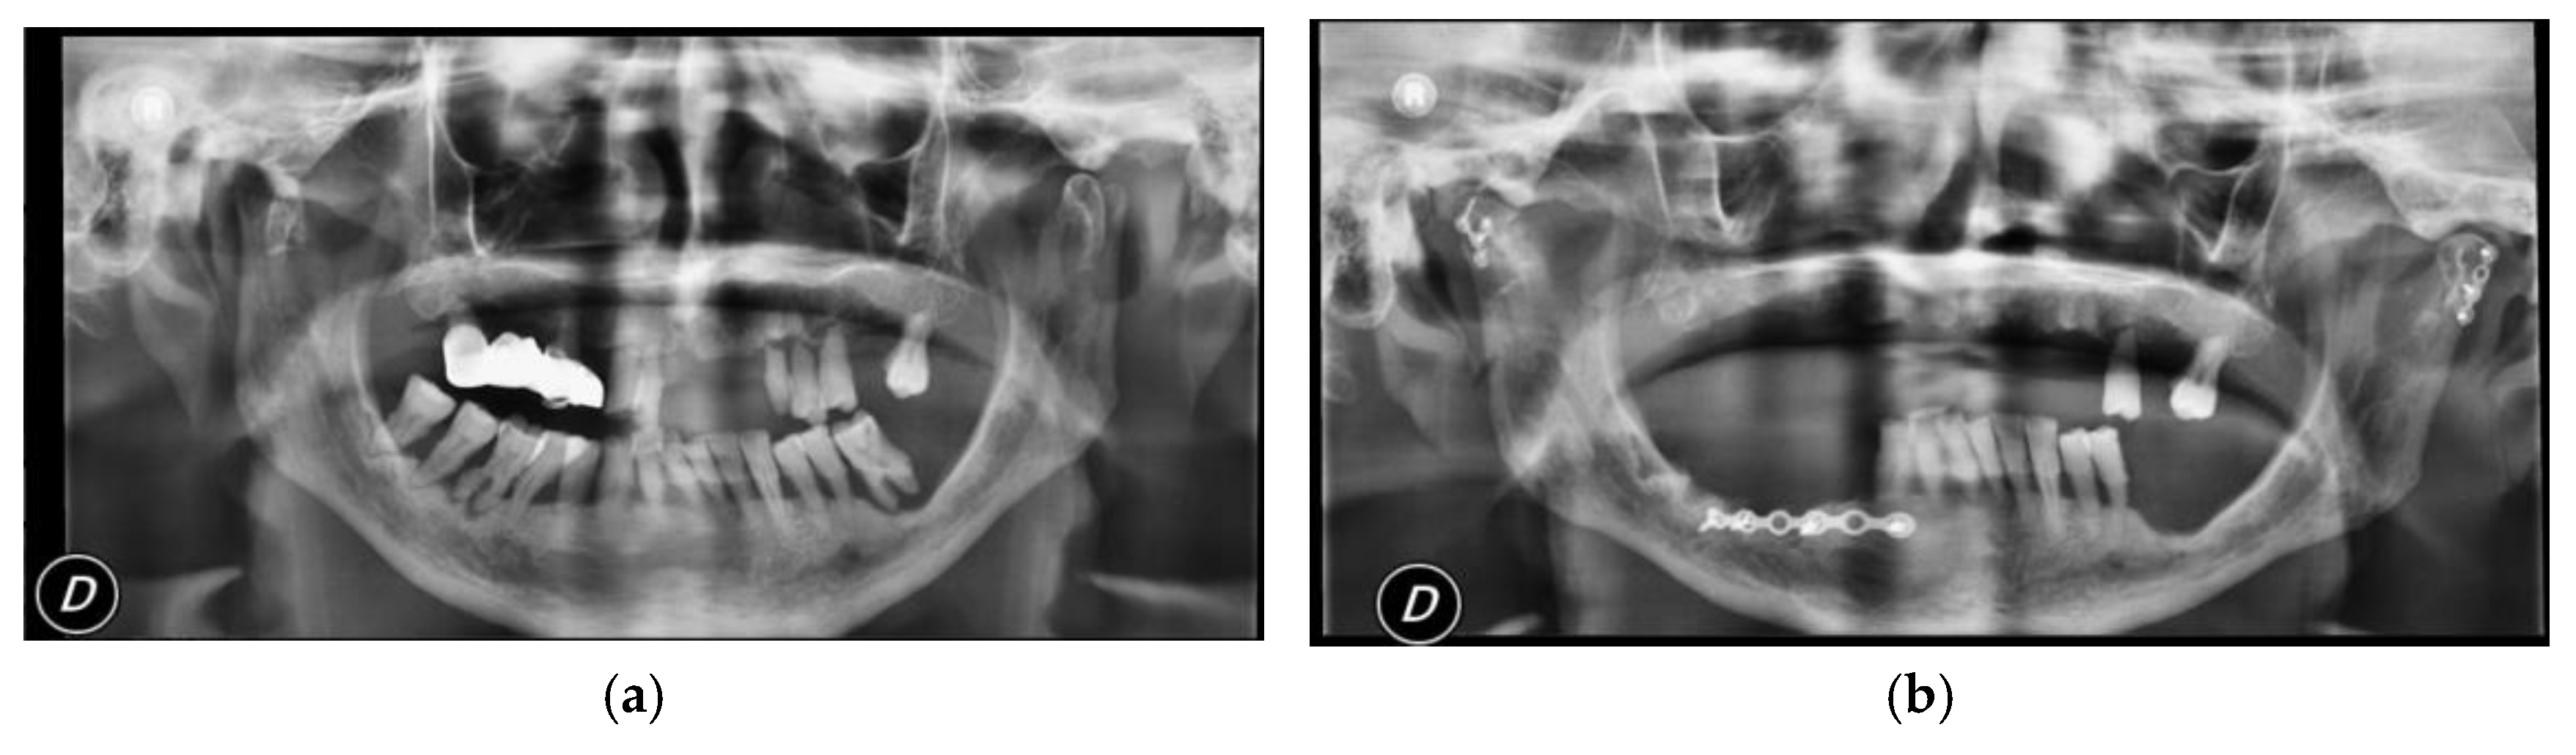

Surgical treatment was performed in patients with widely displaced fractures with lack of contact between the two fragments (Figure 1, Figure 2, Figure 3 and Figure 4), or when the displacement of the fragments caused a lack of function of the TMJ that could not be resolved with conservative treatments, or in multiple fractures of the middle third of the face in order to use the mandible as a guide for replacement of the bones of the middle third of the face, as previously described [8].

Figure 3. (a) Pre-operatory panoramic X-ray; (b) post-operatory panoramic X-ray of patient #3.